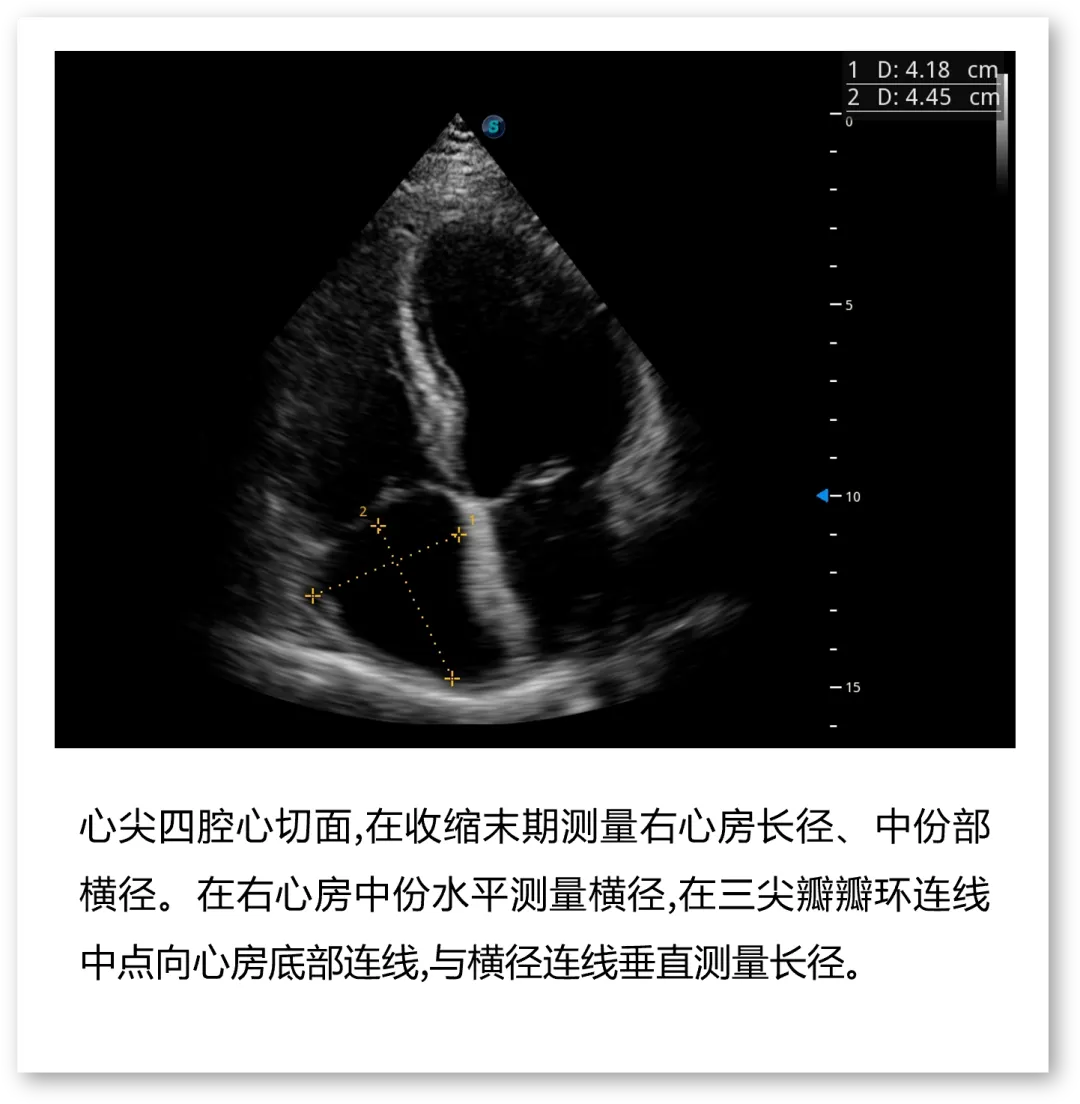

开立医疗联合武汉大学中南医院心血管病医院,将《心脏超声检查规范化中国专家共识 (2024版)》内容与实际临床工作需求融合,精心制作了指南挂图,助力标准采集,规范测量,期待这份实用且高清的工具,能成科室提升超声质效的助手!